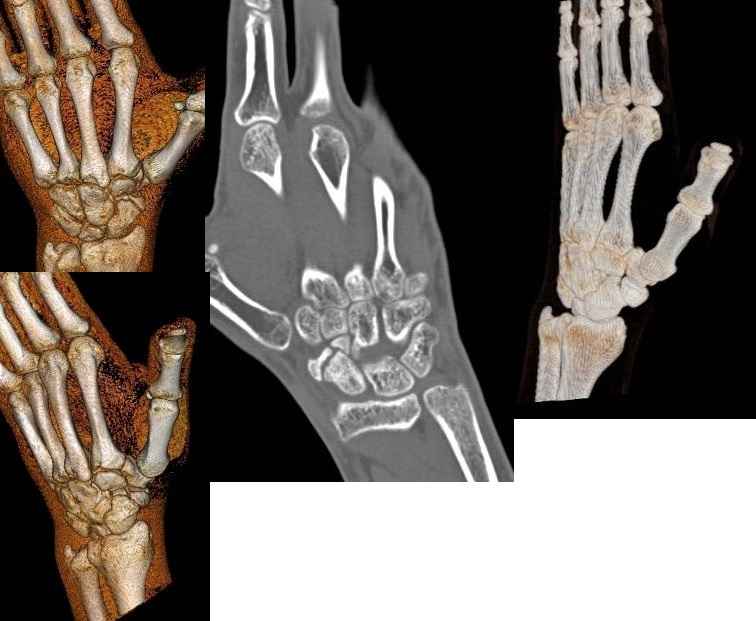

Обратился пациент с несросшимся переломом ладьевидной кости правой кисти

В нашу клинику обратился пациент 23 лет с несросшимся переломом ладиевидной кости правой кисти. Лечился он консервативно, в травм. пункте, результат неудовлетворительный.Хотелось бы выслушать Ваше мнение по поводу его дальнейшего лечения.

Дополняю, прошло 2,5 мес. после травмы, лечился в травм. пункте, гипсовой лангетой, затем циркулярной повязкой. После снятия гипса сращение не наступило.

КТ и компьтерная реконструкция в приложении.

Вообще-то где-то я видел, что перелом ладьевидной кости считается свежим (acute) до 3-х месяцев после травмы. Весьма странно, что перелом в таком благоприятном и хорошо кровоснабжаемом месте не срастается. А обычные свежие рентгенограммы не можете показать? И еще: канюлированый винт-то хорошо, но очень похоже, что имеются два дистальных фрагмента ладьи. Как синтезировать небольшой кусочек? И что беспокоит все-таки больного? А кроме всяких сложных методик лечения , включая и сосудистую реконструкцию, есть еще абсолютно дурацкое предложение. Боюсь даже озвучивать.